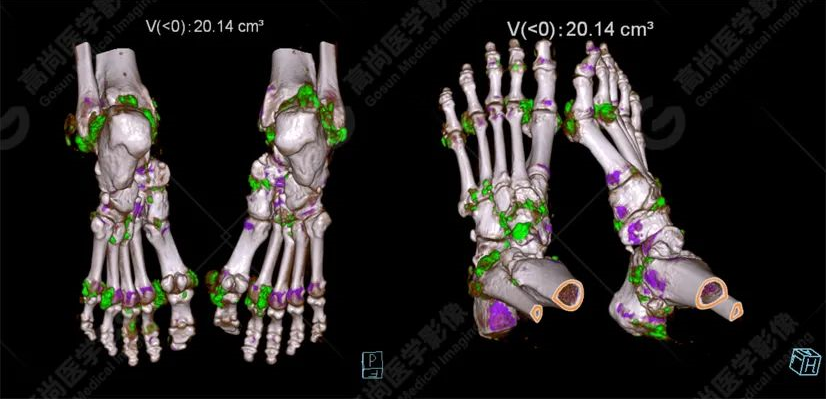

雙足VR圖像

影像表現(xiàn)

雙能CT痛風染色圖像:

白色箭頭提示痛風石沉積。